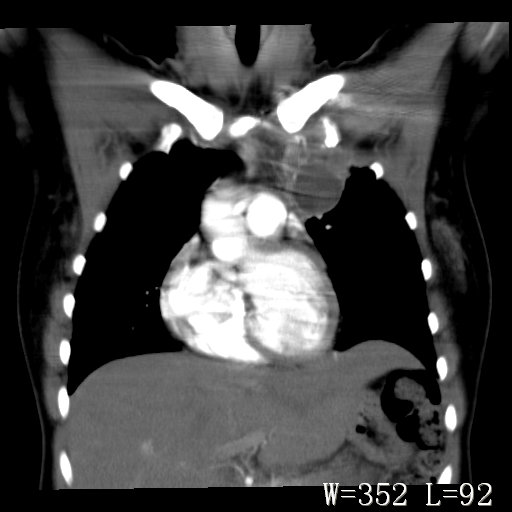

标题: CT27017:1、肺结核?2、永存左上腔静脉。

女,32岁,自述肺结核治疗多年复查。

1)考虑左肺上叶肺脓肿,节段性肺不张。2)永存左上腔静脉。

1)考虑左肺上叶节段性肺不张。原因?2)永存左上腔静脉。

考虑左肺上叶胸腺瘤可能性大。肺不张/永存左上腔静脉

1、胸骨后偏左侧囊实性病灶,考虑胸腺瘤可能性大。2、永存左上腔静脉。